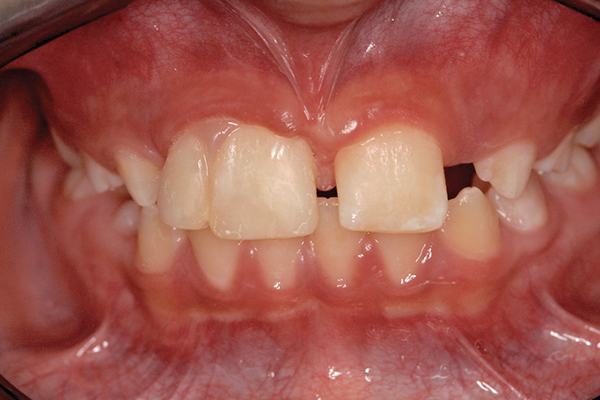

A 9-year-old girl, referred to a prosthodontic office by her pediatric dentist, presented with her mother’s chief complaint: “The kids are teasing her about her big front tooth.” Findings from radiographic and clinical examinations revealed fused maxillary central-peg lateral incisors, teeth Nos. 7 and 8, and a congenitally missing lateral incisor, tooth No. 10 (Figure 1 through Figure 3). An implant was selected as the ideal treatment to replace tooth No. 10 when somatic growth was complete. A diagnostic wax-up was fabricated to determine if the fused tooth could be made to resemble two teeth, using pink composite to give the illusion of an interproximal papilla. The patient was referred for an orthodontic consultation to plan for closure of the diastema between teeth Nos. 8 and 9 and achievement of proper alignment for implant No. 10. The patient was also referred to a periodontist for pretreatment assessment of the tooth No. 10 site. An endodontist was consulted should exposure of the large pulp occur during tooth preparation.

Fig 1 and Fig 2. Pretreatment photographs. Patient at 9 years of age on presentation.